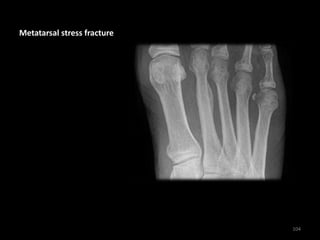

Metatarsal stress fracture

104

• Subtle periosteal stress

reaction of the 2nd

metatarsal

• History of chronic pain

worsened by activity

• Note: Stress fractures

are not always visible

on the initial X-ray - if

suspected repeat X-ray

or MRI may be

required